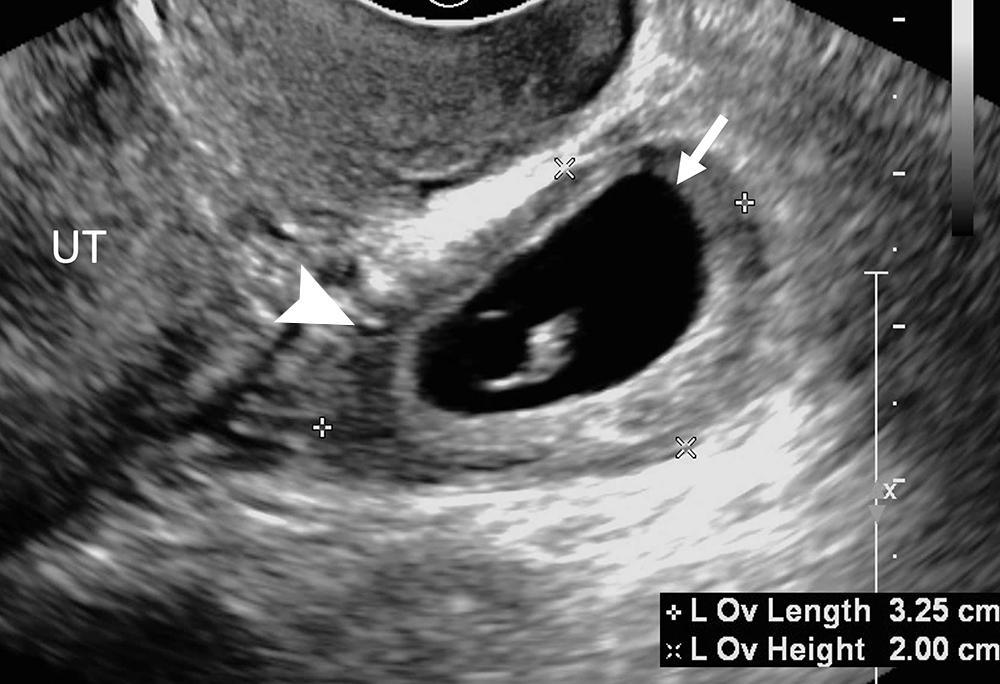

Figure 8. Heterotopic pregnancy. Transvaginal transverse grayscale US image in a 27-year-old pregnant patient shows an early intrauterine pregnancy (IUP) (solid arrow) containing a yolk sac and a tubal ring of ectopic pregnancy (EP) (arrowhead) also containing a yolk sac. The coexistence of an IUP and EP is termed heterotopic pregnancy. The left ovary contains a corpus luteum (dotted arrow) and is seen in the center. The rim of chorionic tissue in the IUP and EP is hyperechoic, whereas in contrast, the corpus luteum is hypoechoic. Echogenicity can help distinguish a tubal ring from a corpus luteum in some cases. UT = uterus.